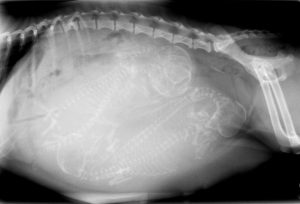

At All Animal Health Care in Aledo, IL, we are proud to be on the cutting edge of medical technology. Radiology is a technique and diagnostic tool that we use to look inside the body in an entirely non-invasive way. X-rays allow us to create images of all the body’s organs.

In other words, the use of radiology gives us a view of the internal organs in your pets’ body that we otherwise could not see. It is a valuable diagnostic tool that helps veterinarians detect and prevent illness.